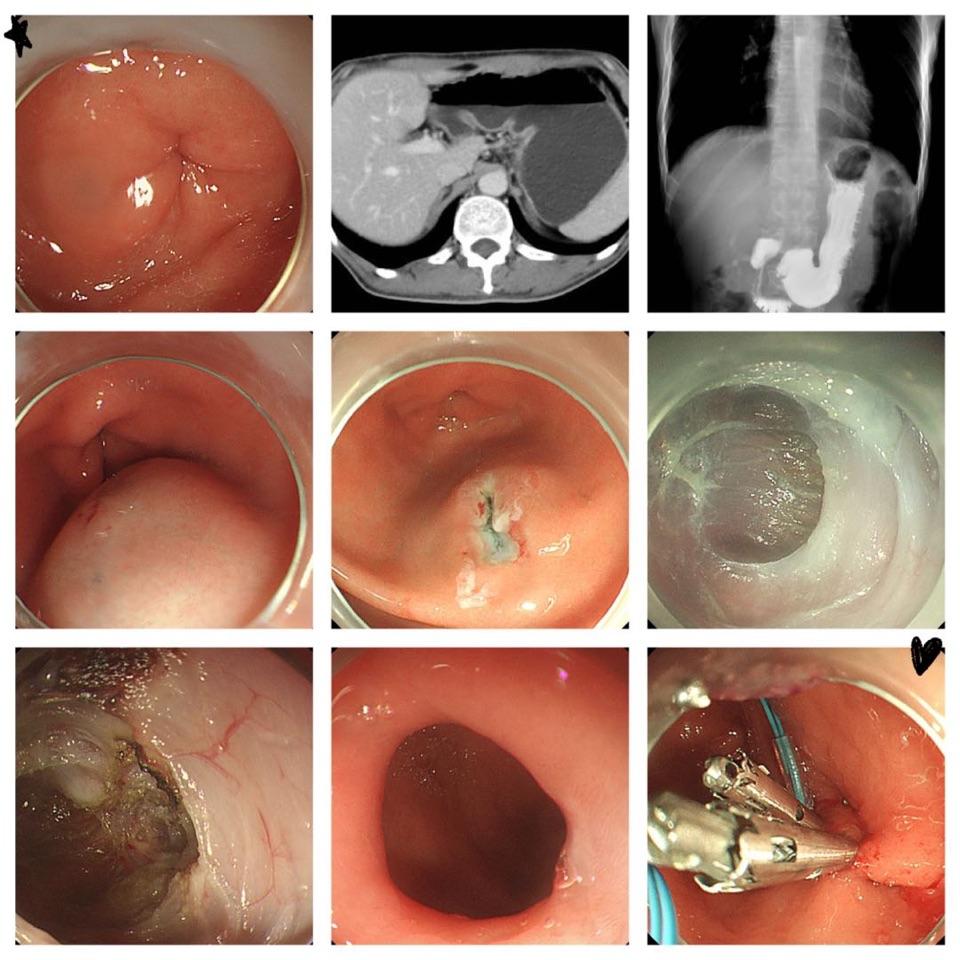

图一  内镜下G-POEM术治疗糖尿病胃轻瘫患者

图释:术前内镜检查提示幽门口痉挛紧闭,空腹CT提示胃内容物多,胃潴留;消化道造影提示胃内造影剂滞留。行G-POEM手术后,再次观察:幽门明显增大。